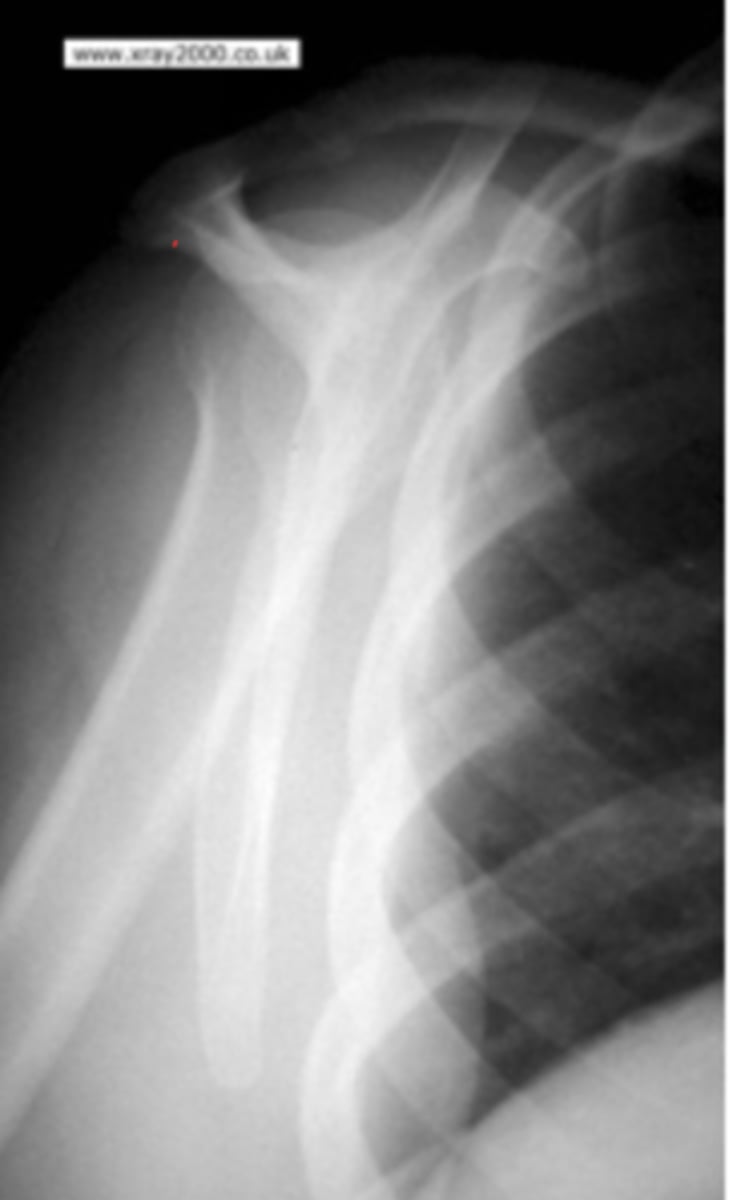

Fracture of the humerus and inferiorly displaced

What is the issue?

pathologic fracture

The sclerotic healing is likely caused by what prior implication?